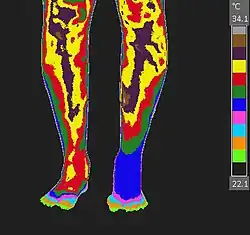

Non-contact thermography, thermographic imaging, or medical thermology is the field of thermography that uses infrared images of the human skin to assist in the diagnosis and treatment of medical conditions. Medical thermology is sometimes referred to as medical infrared imaging or tele-thermology and utilizes thermographic cameras. According to the American Academy of Thermology, Medical Thermology practitioners are licensed health care practitioners who utilize IR imaging in consistent with medically established paradigms of care. Non-medically licensed alternative practitioners who are not held to the same standard may offer thermography services but that should not be confused with the field of medical thermology.

Restated, medical thermology is the use of infrared (IR) imaging to assess skin temperature as an extension of the clinician's physical exam to aid in the formation of a medical diagnosis or treatment plan. Medical Thermology does not condone those who purport that "Thermography" can find disease by looking for areas of the body that have abnormal heat or irregular blood flow. IR imaging simply does not have the ability to assess temperature beyond the surface of the skin.